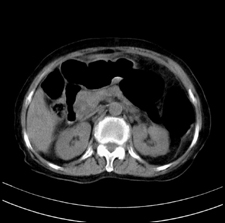

患者,女,75岁。腹痛,体黄5日,膝胸位时腹痛缓解。肝功能明日出来。彩超提示胆总管占位,未见血流信号。心电图提示s-t段改变。患者体质较弱,未能增强。

胆总管多发结石伴肝内外胆管轻度扩张。

胆总管上段,腔内有软组织密度影 ,ct值36-44hu。大家看有没有胆管癌的可能。

2楼所说胰腺内钙化不像,象脾脏血管的钙化

肝囊右.肾上腺囊肿